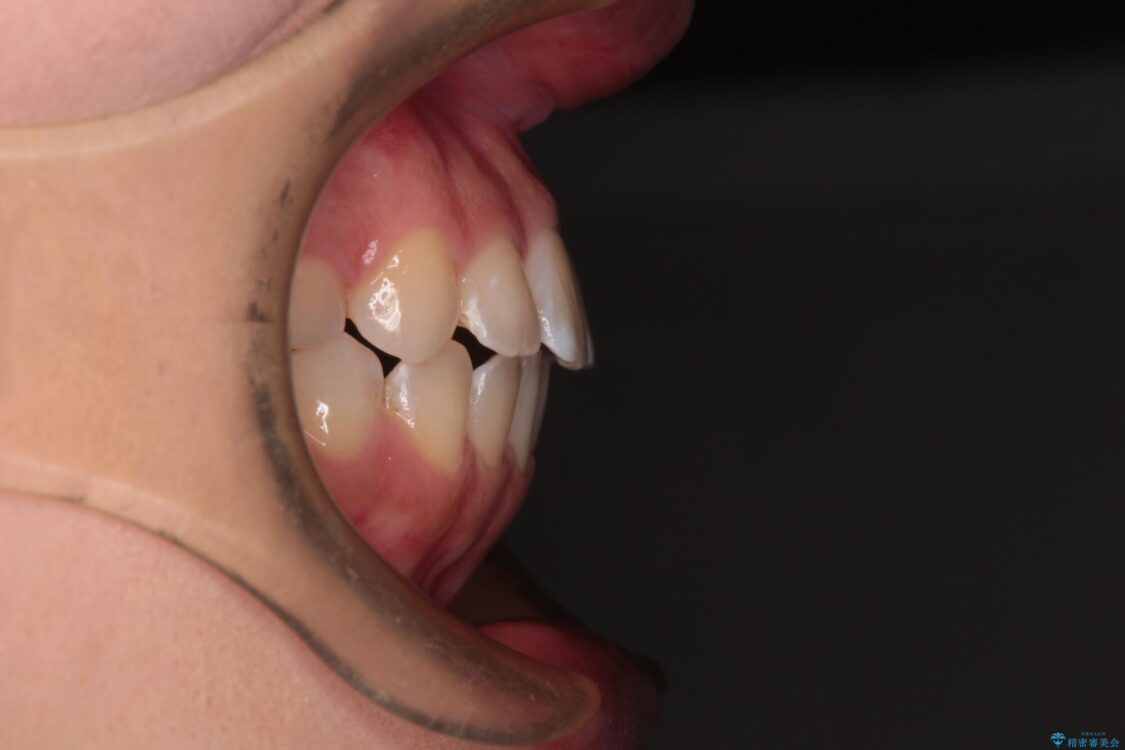

前歯のデコボコを気にして来院された患者様です。

治療前

• 【モニター】短期間で終わりたい ワイヤー装置での非抜歯矯正 治療前画像